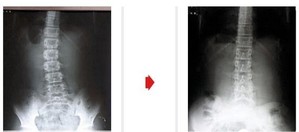

- “건강한 허리를 위해 올바른 걸음걸이 습관가져야”

- 허리는 물론, 목부터 다리까지 전신의 통증을 초래하는 허리디스크의 원인 중 80%가 잘못된 걸음걸이 때문이라는 연구 결과가 발표되었다. 연구 결과에 대해 의문을 갖는 이들도 있을 것이다. 허리에 부담을 주는 특정한 자세에 의해 디스크 ...